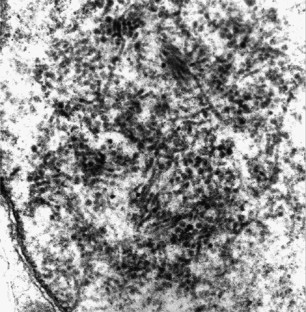

Progressive multifocal leukoencephalopathy (PML) is a rare subacute demyelinating disorder of the central nervous system (CNS) caused by the DNA JC human polyomavirus. In immunocompromised hosts, PML is caused by reactivation of a latent infection rather than de novo primary exposure. PML in the setting of hematopoietic cell transplantation (HCT) is exceedingly rare. PML should be considered in the differential diagnosis of HCT recipients, autologous or allogeneic, presenting with worsening of neurological symptoms, especially associated with post-transplant neurodegenerative findings. Although DNA polymerase chain reaction (PCR) of the cerebrospinal fluid (CSF) has emerged as a promising tool for detecting JC virus, a negative result does not rule out PML. Brain biopsy remains the most reliable and accurate method for diagnosing JC virus-associated PML. Presently, there is no universally effective antiviral therapy against JC virus and outcome is fatal in the majority of cases. We hereby describe two cases of PML developing after allogeneic HCT and provide a comprehensive review of the literature.

Mesquita R, Parravicini C, Bjorkholm M, Ekman M, Biberfeld P . Macrophage association of polyomavirus in progressive multifocal leukoencephalopathy: an immunohistochemical and ultrastructural study. Case report. APMIS 1992; 100: 993–1000.

Kharfan-Dabaja, M., Ayala, E., Greene, J. et al. Two cases of progressive multifocal leukoencephalopathy after allogeneic hematopoietic cell transplantation and a review of the literature. Bone Marrow Transplant 39, 101–107 (2007). https://doi.org/10.1038/sj.bmt.1705548